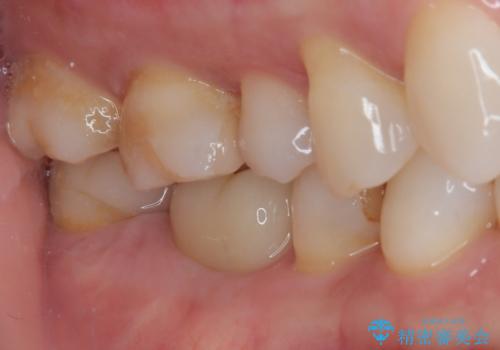

- 今回は、「右上の詰め物が欠けてしまった」という主訴で来院された、40代女性の患者さんの症例をご紹介します。

診察の結果、上顎右側第二小臼歯に装着されていた詰め物の一部が欠けている状態でした。一見すると小さな欠けに見えますが、詰め物が破損した部分はプラーク(歯垢)が非常に溜まりやすく、虫歯の再発リスクが高い状態になります。

まず、欠けていた詰め物と、その下に存在していた虫歯をすべて丁寧に除去しました。その後、適合性・耐久性・審美性に優れたセラミックインレーを用いて修復処置を行いました。